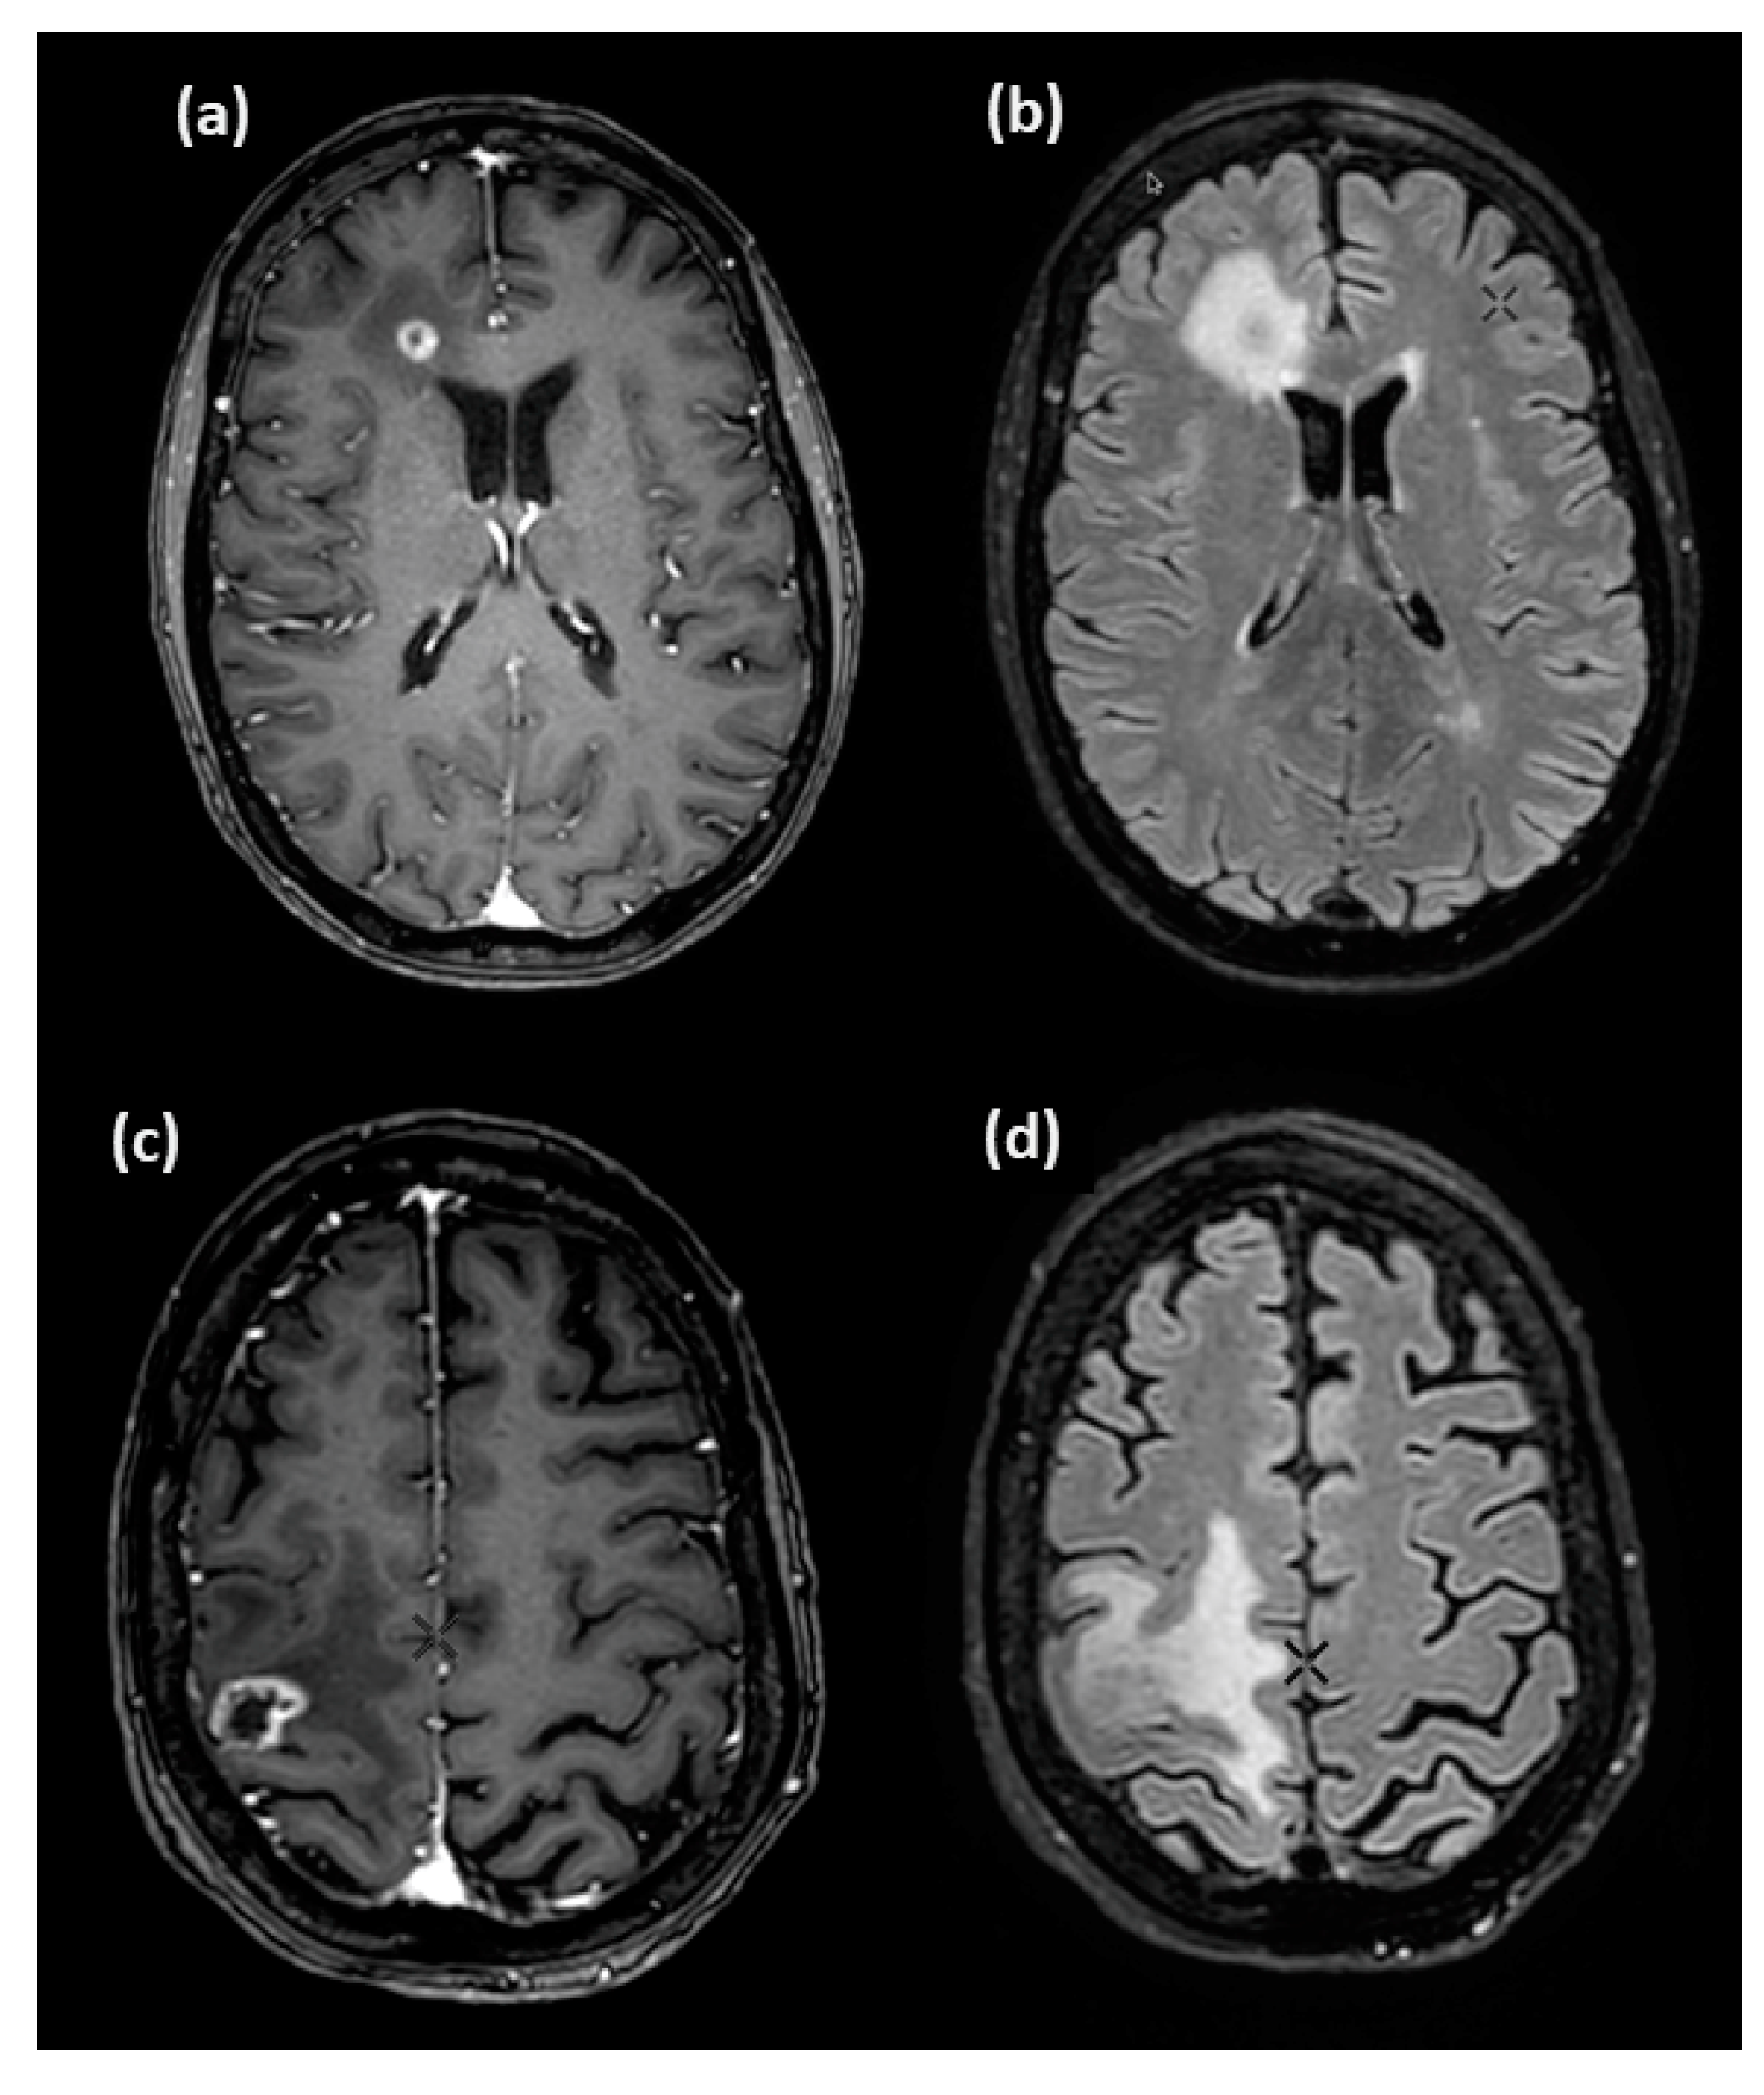

2.2. [18F]F-DOPA PET/CT Imaging

2.3. In-House MATLAB Software Tool

2.4. Experimental Volumes

2.5. The Clinical Volume